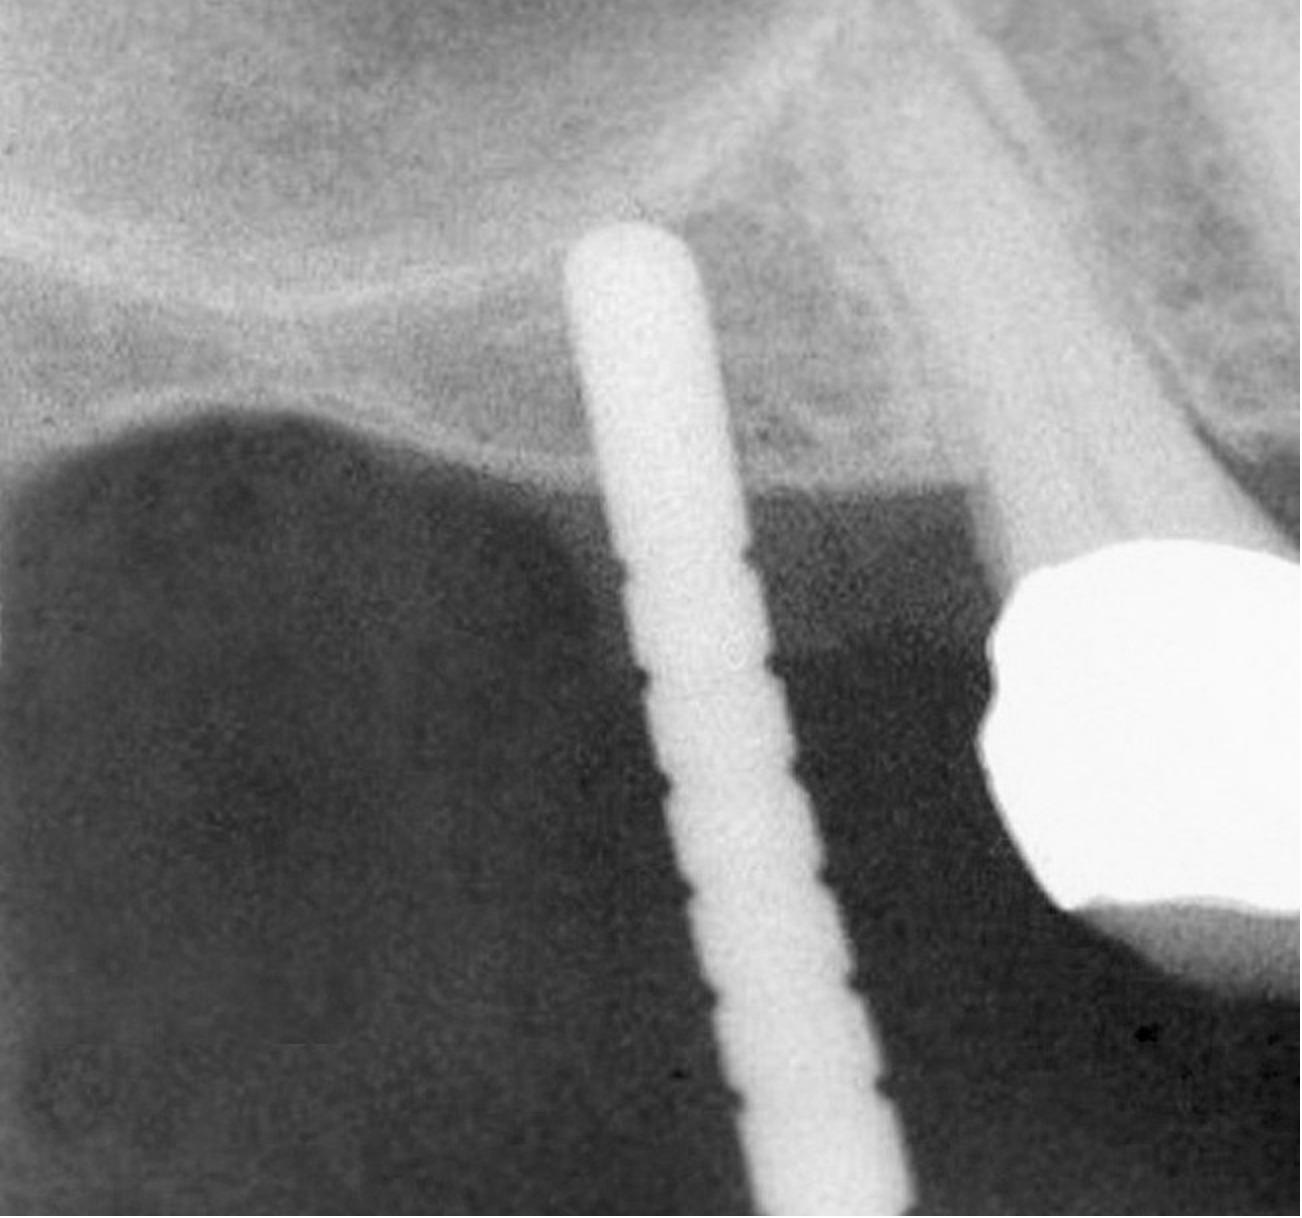

Accidental Penetration of Sinus Membrane with First Twist Drill

When using a 2-mm twist drill, the sinus could inadvertently be entered. This incursion can be verified by occluding the patient's nostrils and having the patient blow (Valsalva maneuver). If the membrane has been perforated, air bubbles will appear in the osteotomy. Some clinicans indicate that if a perforation has occurred, the sinus floor elevation procedure should be aborted and the site should be allowed to heal for 4 weeks and then redone.4 However, the situation may be salvageable (Figure 12, Figure 13, Figure 14, Figure 15). The amount of bone that is subantral can be re-evaluated, and then the second drill (eg, 2.8-mm wide) used, making sure not to enter the sinus. Similarly, the third drill (3.5-mm wide) can be used to proceed 1 mm short of the sinus floor. The initial sequence should be followed with respect to adding bone; whether or not a dome has formed should be verified radiographically. If the graft material is contained, then the procedure can be brought to conclusion as if a perforation had not occurred. On the other hand, if the material was not contained, it may appear on the radiograph as a "trail of smoke." In this case the procedure needs to be aborted or a lateral wall sinus lift needs to be performed to complete the task and repair the perforated membrane. In general, the ostium is 2.4-mm wide;33 it ranges from 2.14 mm to 6.77 mm.34 Therefore, particles that have escaped through the membrane will probably be swept through the ostium by the ciliated columnar epithelium without any untoward occurrence. Other authors have also noted that a perforation of the membrane does not necessarily result in failure of an implant that penetrates into the sinus.35

Figure 12  Initial radiograph at site No. 3.

Figure 12

Figure 13  Despite initial perforation into the sinus with the 2.1-mm twist drill, the drilling sequence was continued after the drill depth was adjusted to be 1 mm short of the subantral floor. The radiograph demonstrates that after the subantral floor was up-fractured and bone was added via the osteotomy, the initial puff of bone was contained. Therefore, the procedure could continue.

Figure 13

Figure 14  Additional bone was added via the osteotomy.

Figure 14

Figure 15  Implant successfully placed.

Figure 15